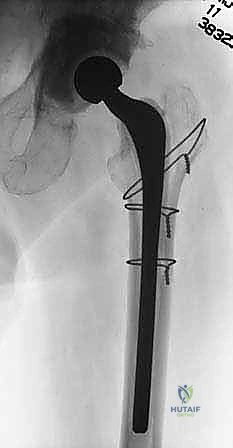

4. تحضير ووضع "الفاصل المحمل بالمضادات الحيوية" (Antibiotic Spacer)

ما هو الفاصل الإسمنتي؟ هو جهاز مؤقت يتم تشكيله أثناء العملية باستخدام "إسمنت العظام" الطبي (Polymethylmethacrylate - PMMA).

* السر الطبي: يتم خلط هذا الإسمنت بجرعات عالية جداً من المضادات الحيوية (مثل الفانكومايسين والتوبيمايسين) التي تتحمل الحرارة العالية الناتجة عن تصلب الإسمنت.

* آلية العمل: بمجرد وضعه داخل تجويف الورك، يبدأ الفاصل في إطلاق تركيزات هائلة من المضادات الحيوية موضعياً داخل المفصل، بتركيز يفوق مئات المرات ما يمكن تحقيقه عبر الدم، مما يقضي على أي بكتيريا متبقية في العظم.

* أنواع الفواصل:

* فواصل ثابتة (Static): كتل إسمنتية تمنع الحركة تماماً، تُستخدم في حالات فقدان العظم الشديد.

* فواصل مفصلية (Articulating): تشبه المفصل الحقيقي، تسمح للمريض بثني الورك والمشي الخفيف، مما يحافظ على مرونة العضلات ويسهل الجراحة الثانية. وهو النوع الذي يفضله د. هطيف متى ما كانت حالة العظم تسمح بذلك.